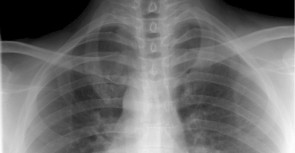

Knowledge 大師學堂 首頁 大師學堂 生活知識 全部分類 換氣知識 產品知識 生活知識 生活知識 阿根廷不明原因肺炎4死 病因指向退伍軍人症 退伍軍人症最初是在1976年美國退伍軍人協會於費城召開會議時出現,和受到汙染的水、以及不乾淨的空調系統有關,因為患者大多為退伍軍人,因此稱為退伍軍人症。 生活知識 虔誠燒香6年竟罹肺癌!避免吸入致癌物4個居家秘笈 拜拜中產生PAHs是肺腺癌高風險因素,會破壞體內遺傳物質,廚房油煙也含大量PM2.5,不使用排風裝置罹癌機率增3-12倍。